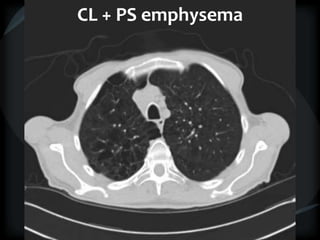

Emphysema - CL

CL + PS emphysema

Hyperlucency

Centrilobular emphysema

Paraseptal emphysema

CL + PSemphysema